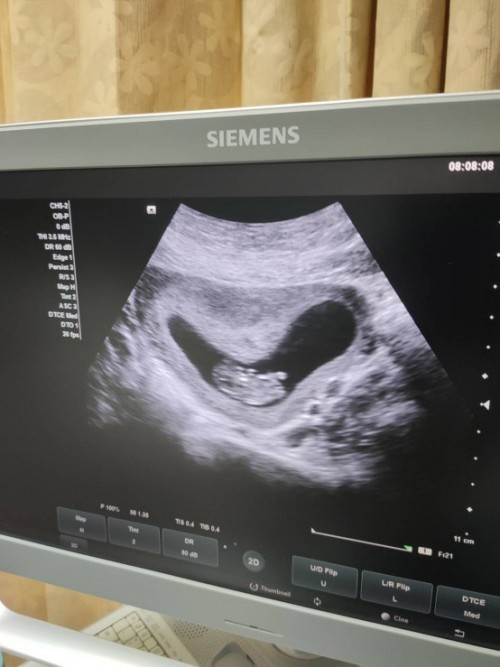

บ้านนี้10+5วีคค่ะ

10w 4cm ตอนนี้13w 6cmค่าา

10W ยาว4เซน แล้วค่ะ